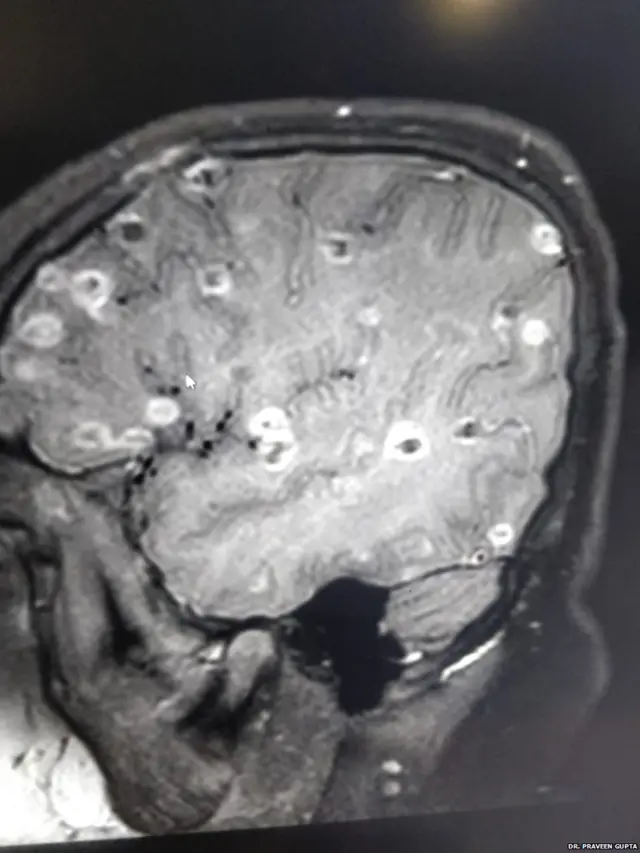

"बच्ची के दिमाग़ में 100 से ज़्यादा टेपवर्म यानी फ़ीताकृमि के अंडे थे. जो दिमाग़ में छोटे-छोटे क्लॉट (थक्के) के रूप में नज़र आ रहे थे. "

डॉक्टर गुप्ता बताते हैं "जिस समय बच्ची को अस्पताल लाया गया वो होश में नहीं थी. सिटी स्कैन में सफ़ेद धब्बे दिमाग़ में नज़र आए. ये धब्बे कुछ और नहीं बल्कि फ़ीताकृमि के अंडे थे. वो भी एक या दो नहीं बल्कि सौ से ज़्यादा की संख्या में."

जब बच्ची डॉ. गुप्ता के पास पहुंची तो उसके दिमाग पर प्रेशर बहुत अधिक बढ़ चुका था. अंडों का प्रेशर दिमाग़ पर इस कदर हो चुका था कि उसके दिमाग़ ने काम करना बंद कर दिया था.

डॉ गुप्ता बताते हैं, "सबसे पहले तो हमने दवाइयों से उसके दिमाग़ का प्रेशर (दिमाग़ में कोई भी बाहरी चीज़ आ जाए तो इससे दिमाग का अंदरूनी संतुलन बिगड़ जाता है) कम किया. उसके बाद उसे सिस्ट मारने की दवा दी गई. ये काफी ख़तरनाक भी होता है क्योंकि इस दौरान दिमाग़ का प्रेशर बढ़ भी सकता है."